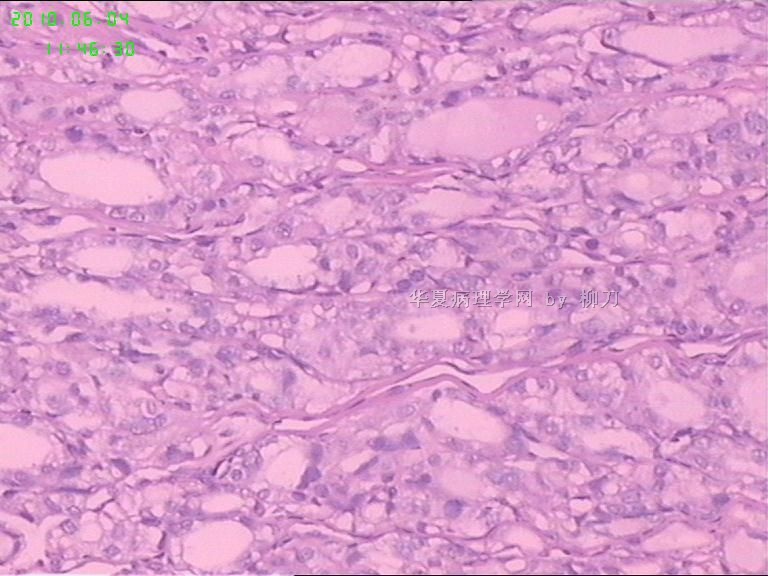

灰白结节2枚,其一2.5x1.8x1.5cm,包膜完整,内为褐色胶质,其二3x2.5x1.5cm包膜完整,切面灰白实性。附件镜下为后者。

结节性甲状腺肿。

可能楼主看到那些核的变化吧?但是没有其他支持的条件,还是应该是结甲。

就这几幅图似乎不够说明问题,细胞有一定的异型性,但是,最好能采到交界处的情况再判断。癌与非癌,最好能有组织结构与细胞异型性结合来看。

有些核透明,无其它特点,恶性证据是没有。

要看肿瘤包膜情况。